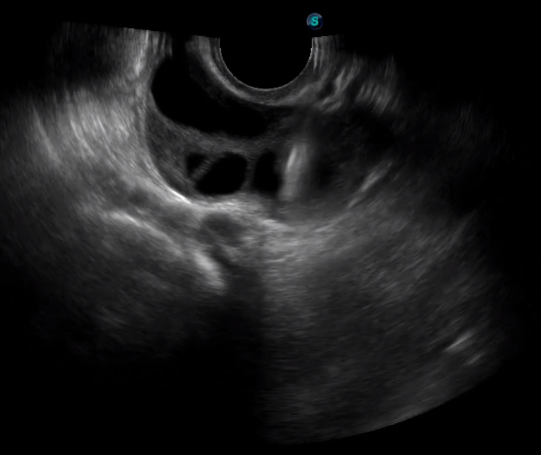

傳統(tǒng)腔內(nèi)探頭采用直柄設(shè)計,在搭配穿刺架使用時,手術(shù)空間小,不易操作;生殖專用的曲柄探頭,探頭柄采用彎曲成角度設(shè)計,可實現(xiàn)監(jiān)視、取卵兩不誤,搭載穿刺架時,可以清晰顯示穿刺針的進針過程、深度和位置,實時監(jiān)視取卵全過程,保障取卵操作精準(zhǔn)與安全。

取卵臨床圖